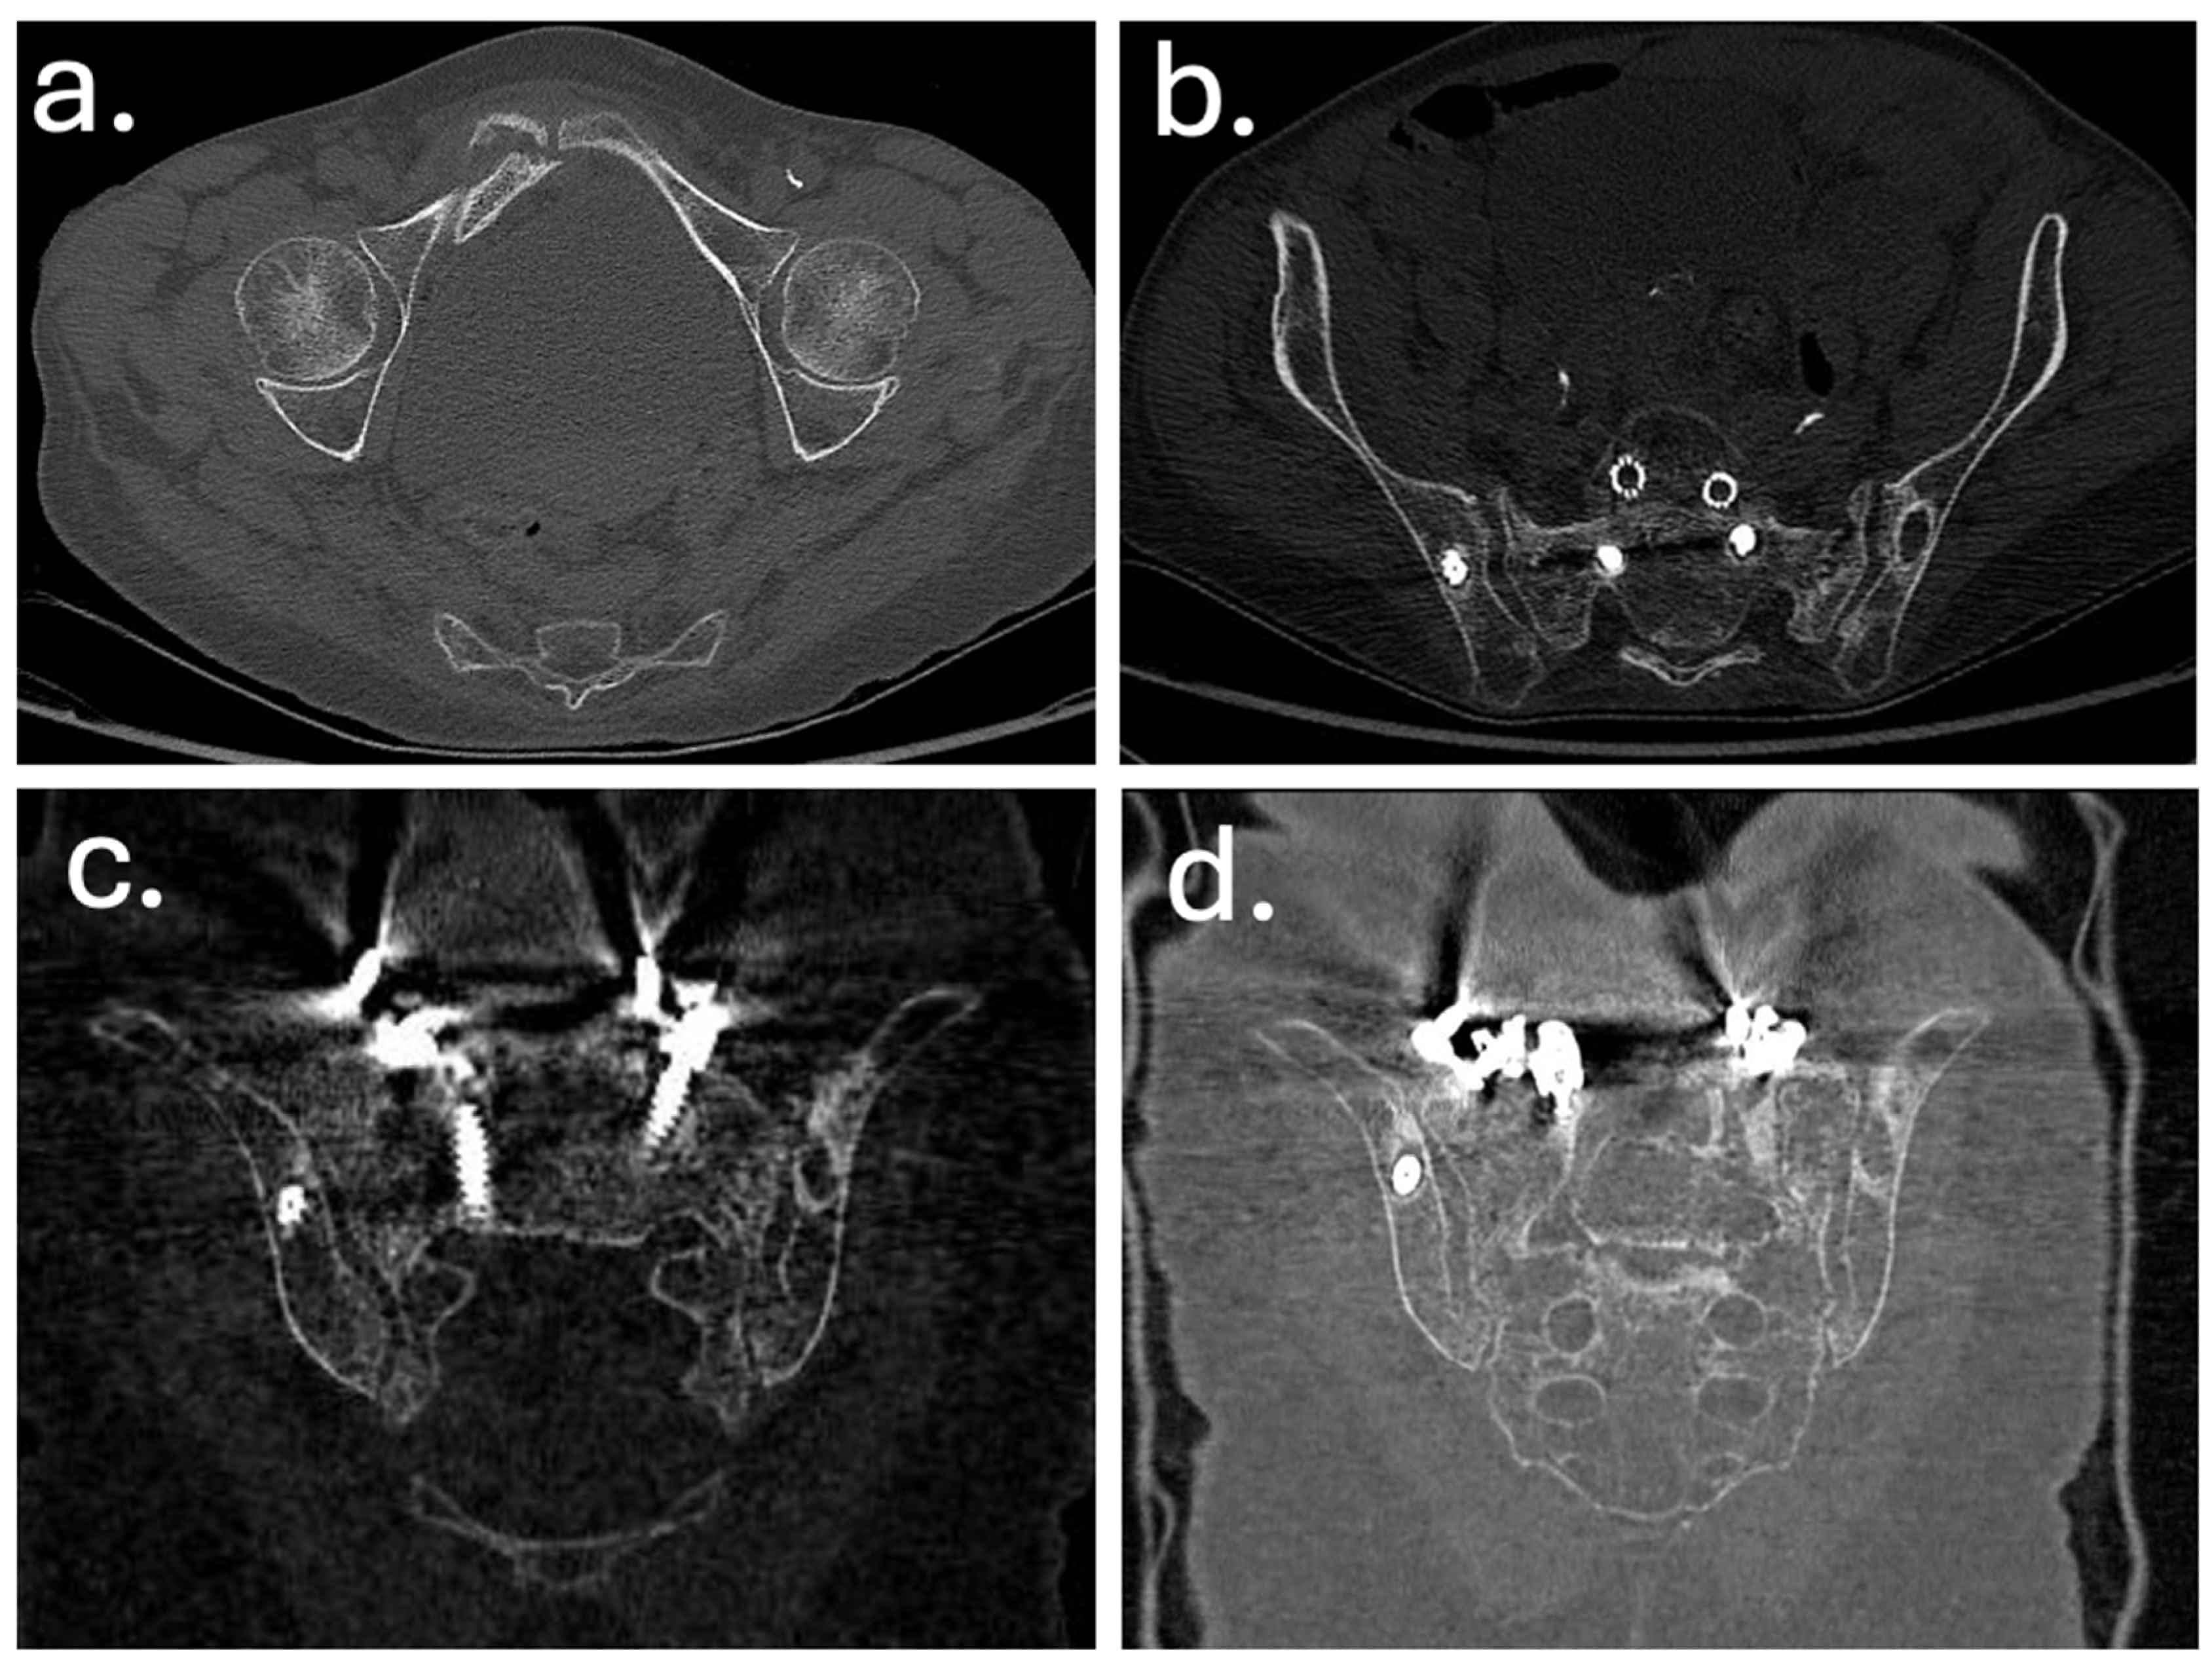

In December 2019, a revision surgery was performed due to partial construct failure and suspected iliac screw loosening as showed in Figure 4 and Figure 5. The left iliac screw and bilateral screws at T4–T5 were removed. New pedicle screws were placed bilaterally at T2–T3, and two additional rods were added, creating a delta-rod four-rod configuration to enhance construct stability and distribute stress.

Figure 4. Computed tomography (CT) images obtained at the time of sacral insufficiency fracture diagnosis. (a) Axial view showing a right ilio-pubic branch fracture. (b) Axial view demonstrating an impacted fracture of the left sacral ala. (c,d) Coronal reconstructions confirming the left sacral ala fracture (c) and illustrating loosening of the iliac screws (d).